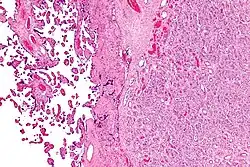

| Placenta with an especially large 10cm chorioangioma | |

Histologically, chorioangiomas consist of abundant vascular channels and may be cellular.